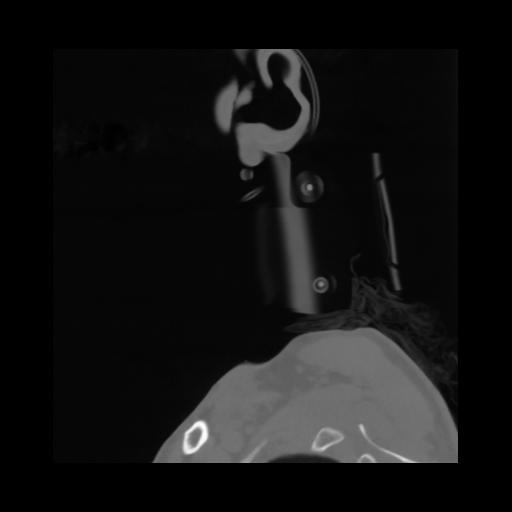

14 P.BLANDAS,,Sagittal,2.000,P.BLANDAS,Sagittal,